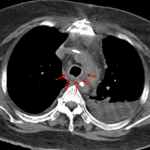

Age: 73

Sex: Female

Indication: Atrial fibrillation, chest pain

CT

- Chest

- Irregular wall thickening of the lower trachea and proximal mainstem bronchi with surrounding mediastinal fat stranding but no pneumomediastinum or mediastinal fluid collection

- Debris layering in the central airways

- Dependent consolidation and groundglass opacification in the right greater than left lower lobes and left upper lobe

- Widespread bronchial wall thickening and interlobular septal thickening

- Trace right pleural effusion

- Endotracheal tube terminates above the carina

- Left subclavian approach central venous catheter terminates in the SVC

- Post-CABG changes with postsurgical stranding/scarring in the anterior mediastinum

- Thoracic aortic atherosclerosis without aneurysm

- Moderate coronary artery calcification

Diagnosis

Irregular thickening of the lower trachea and proximal mainstem bronchi with surrounding fat stranding suggestive of tracheitis/proximal bronchitis with surrounding mediastinitis. No pneumomediastinum or drainable fluid collection.

Multifocal pneumonia, which may relate to aspiration.

Trace right pleural effusion.